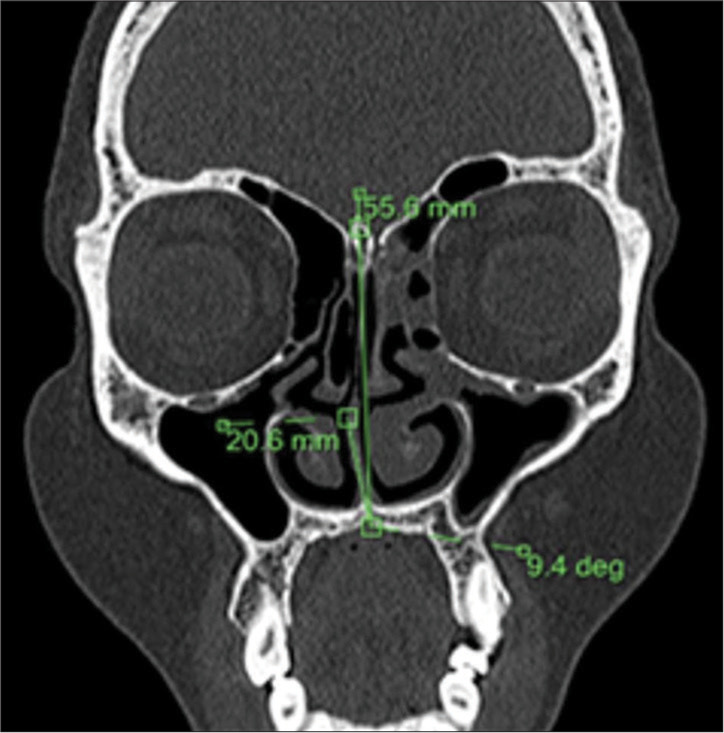

Material and methods: A case-control study was conducted with 103 patients presenting with chronic sinonasal symptoms (cases) and 50 asymptomatic individuals (controls). A 128-slice computed tomography scanner was used to measure maxillary sinus volume and assess anatomical variants, such as a deviated nasal septum (DNS), concha bullosa (CB), and agger nasi cells. Exclusion criteria included previous sinonasal surgery, malignancy, craniofacial trauma, and lack of consent. Statistical analysis was performed using t-tests for continuous variables and Chi-square tests for categorical data. Receiver operating characteristic curve analysis was utilized to determine a DNS angle cutoff for predicting CRS.

Results: Anatomical variants were significantly more frequent in cases than in controls. The left-sided DNS was predominant in cases, while the right-sided DNS was more common in controls. The mean DNS deviation angle was notably larger in cases (10.84° ± 7.87) than in controls (5.55° ± 5.02). Maxillary sinus volume was significantly smaller in cases (9.69 cc on the left side and 10.23 cc on the right side) compared to controls (18.57 cc and 18.46 cc, respectively), with female patients exhibiting smaller volumes than males. Agger nasi cells were detected in 51.5% of cases versus 8.0% of controls. A strong association was found between CB and contralateral DNS. The optimal DNS deviation angle cutoff for predicting CRS was identified as 12.7°.